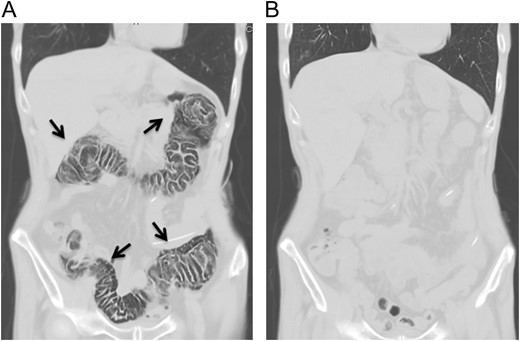

A 70-year-old man visited to our hospital with persistent difficulty in swallowing. He was diagnosed with stage II esophageal cancer by endoscopy, computed tomography (CT) and fluorodeoxyglucose-enhanced positron emission tomography. Because his oral intake was insufficient due to the obstruction of the tumor, he underwent a laparoscopic jejunostomy prior to NAC [3]. At Day 10 after the initiation of the first course of NAC with CF, he experienced slight nausea and abdominal distention, which were treated with antiemetics. At Day 14 after the initiation of NAC, he had severe abdominal pain with lower abdominal tenderness. His body temperature was 37.7 °C and heart rate was 119 beats/min. Blood tests revealed an elevation in the C-reactive protein level (3.7 mg/dL) and renal dysfunction. CT scan revealed the presence of gas within the wall of the entire colon and a small amount of free air in the mesentery (Fig. 1A). Thus, he was diagnosed with PI. A colonoscopy revealed an edema of the mucosa with a white coat, which was not observed before NAC (Fig. 2). Because there were no signs of intestinal ischemia and peritoneal irritation, we treated him conservatively; treatments included cessation of enteral nutrition, administration of meropenem hydrate and selective decontamination of the digestive tract, and oxygenation. The day after the initiation of these therapies, his abdominal pain improved. CT at Day 7 after the PI diagnosis showed that the gas within the wall had disappeared (Fig. 1B). Because NAC with CF was highly suspected to have caused PI, we abandoned the second course of CF therapy. The therapeutic effect of NAC resulted in a stable disease. We carried out video-assisted thoracoscopic esophagectomy on Day 14 after the initiation of NAC. An intraoperative laparoscopy showed no significant findings in the serosa of the colon and no intra-abdominal abnormal adhesions. He was discharged from our hospital without any complications, including PI recurrence.

Abdominal computed tomography at the onset of abdominal pain revealed pneumatosis intestinalis of the colon. No free air was detected (A). Computed tomography 7 days after the diagnosis of pneumatosis intestinalis did not show any gas within the wall of colon (B).